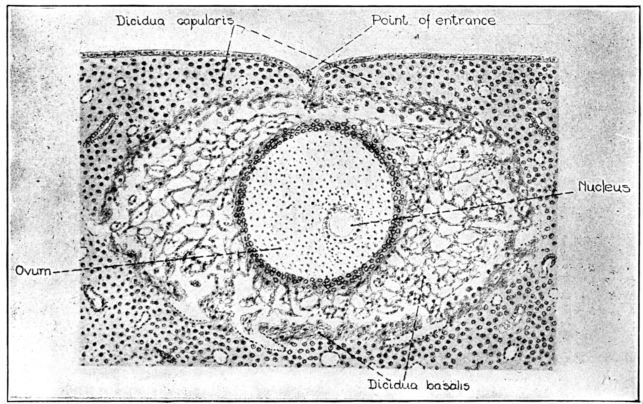

| 19. | Ovum about 13 days old embedded in the decidua | 66 |

| 20. | Diagram of developing fetus, cord, membranes and placenta in utero | 69 |